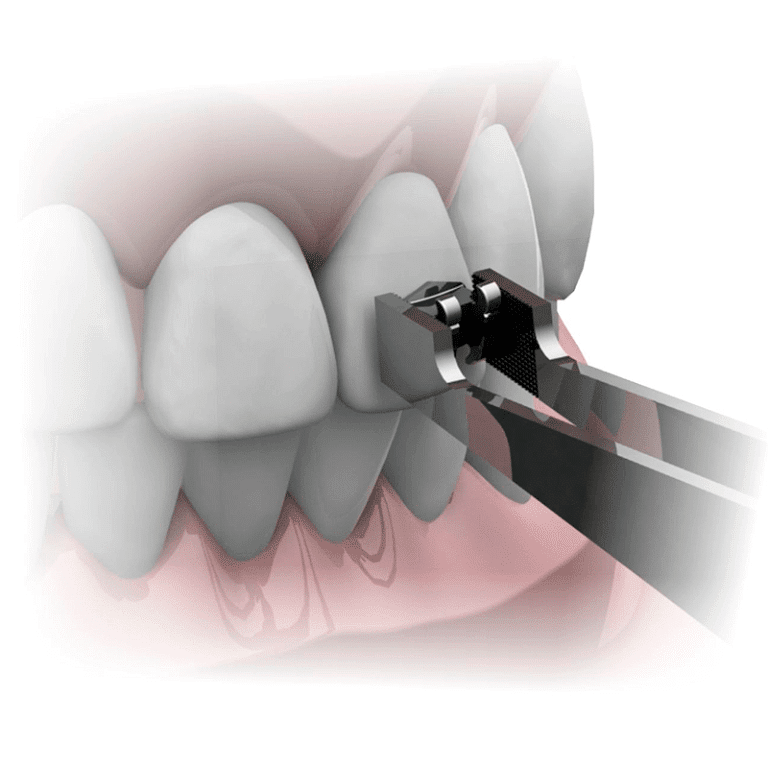

- Alicates e Instrumentos

- Brackets